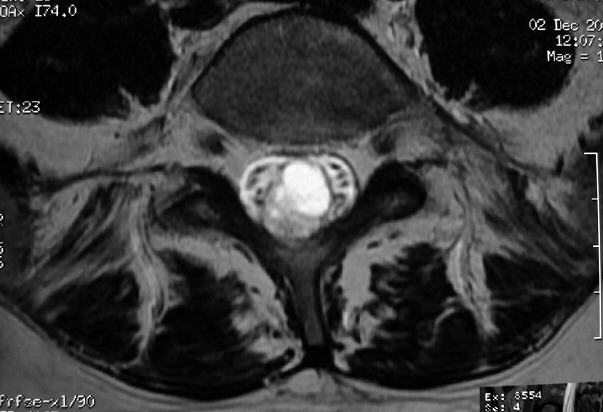

ГМ. СМ. Эпендимома миксопапиллярная. +

Эпендимома миксопапиллярная